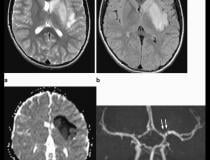

This photo gallery shows the variety of radiological presentations of COVID-19 (SARS-CoV-2) in medical imaging, including computed tomography (CT), radiograph X-rays, ultrasound, echocardiograms and magnetic resonance imaging (MRI). The radiology images show examples of typical COVID pneumonia in the lungs and the numerous complications the virus causes in the body in multiple organs, including the brain, kidneys, heart, abdomen and vascular system.